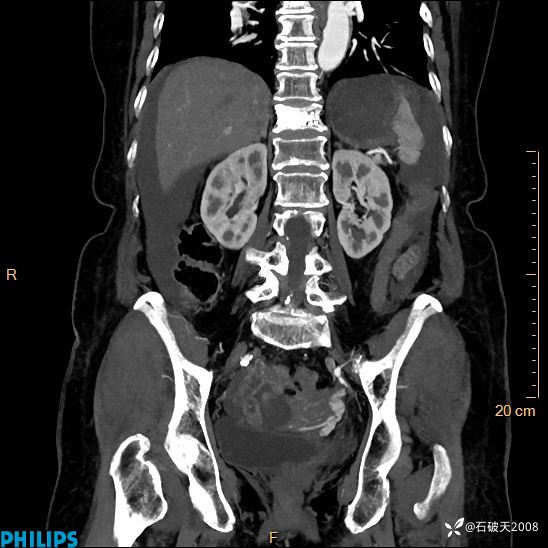

静脉期